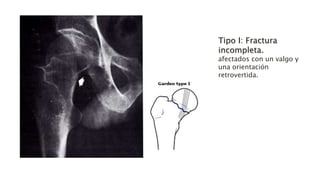

•Tipo I: Fractura incompleta o en abducción (impactada en valgo).

Tipo I: Fractura

incompleta.

afectados con un valgo y

una orientación

retrovertida.

Tipo I: Fractura incompleta. afectadoscon un valgo y una orientación retrovertida.